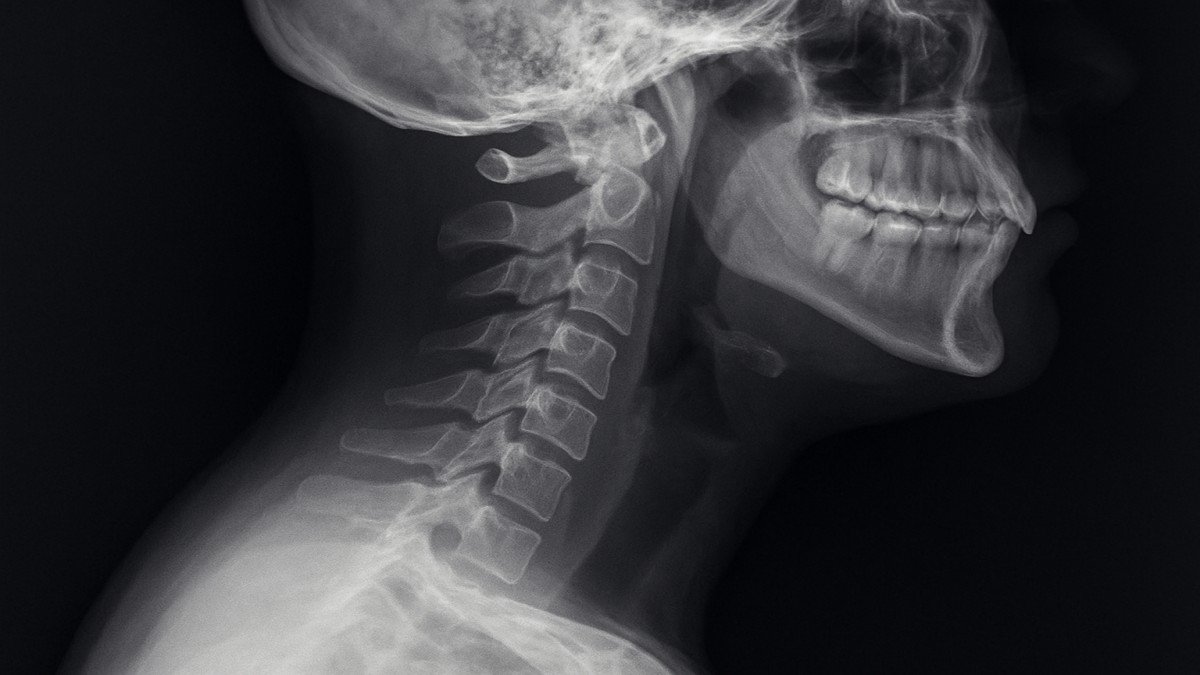

It refers to the inward curvature of the cervical spine, located in your neck. A healthy cervical lordosis helps distribute mechanical stress and allows smooth movement.

Anatomy of the Cervical Spine

Structure of the Neck Vertebrae

Your cervical spine has seven vertebrae (C1–C7). These bones support your skull, protect the spinal cord, and allow motion such as turning, bending, and tilting.

X-rays and Imaging Tests

These show the degree of curvature and any structural abnormalities.